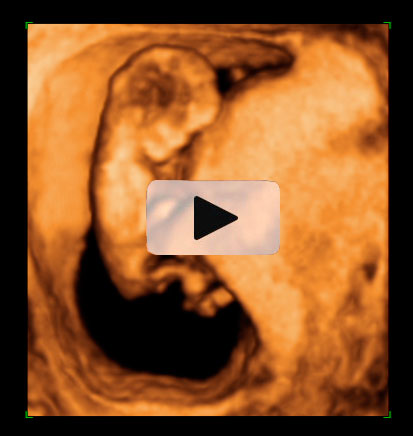

Ecografía 4D semana 12: Bebé moviendo brazos y piernas

La ecografía 4D muestra un bebé de 12 semanas de gestación moviéndose con gran vitalidad dentro del útero materno. Se percibe perfectamente que el feto tiene formadas todas sus estructuras básicas, a falta de que maduren a lo largo del embarazo.

Ecografía en 4D de bebé de 12 semanas moviendo brazos y piernas

La vitalidad del bebé es increíble. Mueve brazos y piernas con energía, como si estuviera nadando, o haciendo un "sprint" final. En realidad está apoyado en la pared uterina de su madre. Se perciben las estructuras básicas del feto con gran claridad: cabeza, aún muy grande respecto al cuerpo, tronco y extremidades. Este movimiento es uno de los signos de vitalidad fetal que los ecografistas siempre evalúan en sus exploraciones.